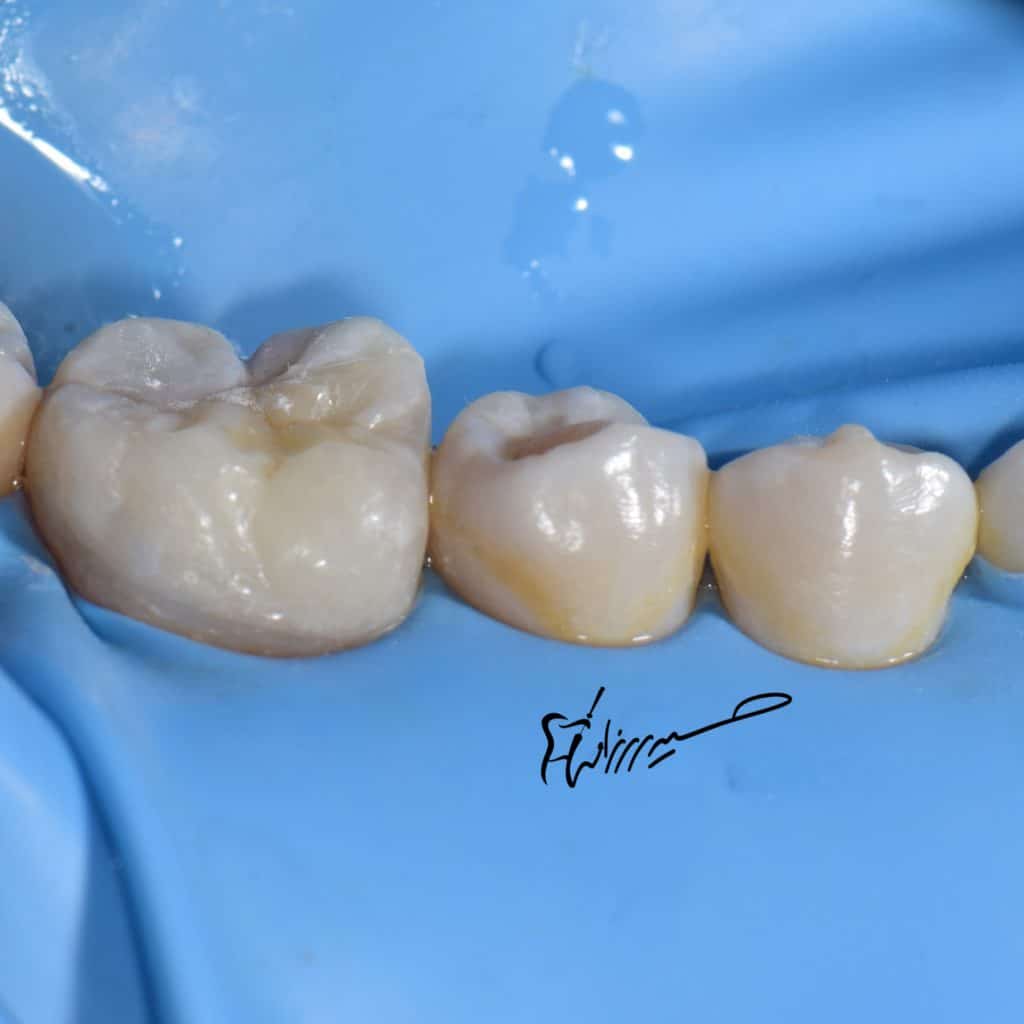

Non retentive lithium disilicate restoration

Before cementation